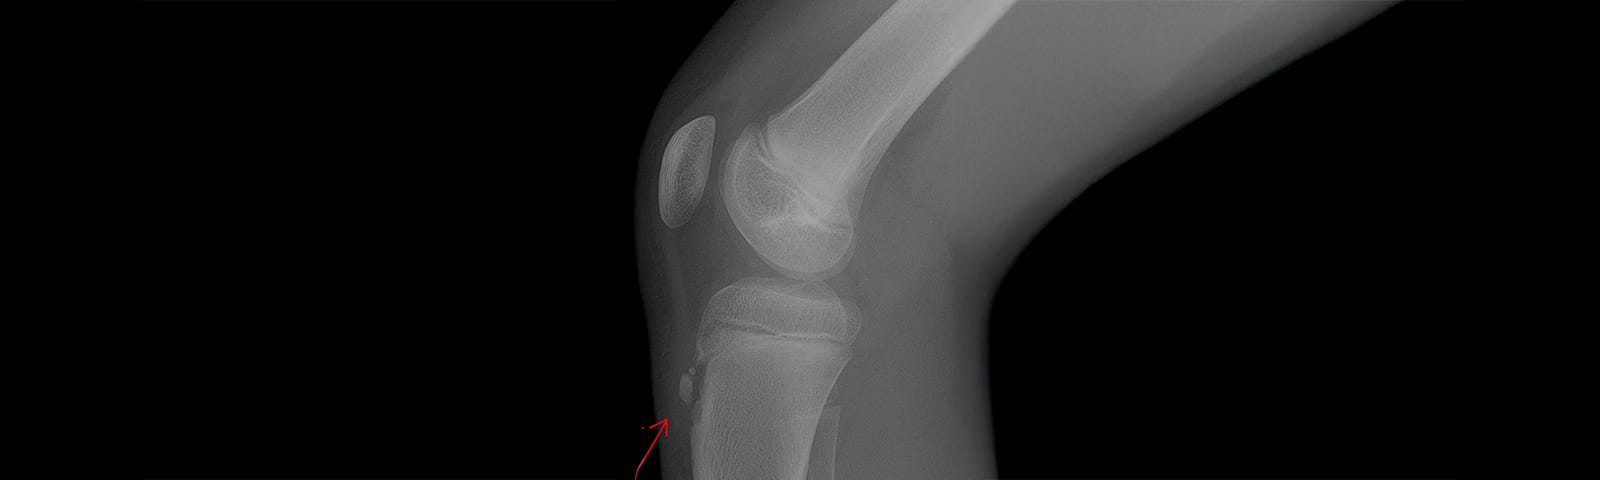

Sindrome di Osgood – Schlatter in un soggetto adulto. Trattamento con Tecarterapia

La tecarterapia può rivelarsi molto utile nel trattamento di questa sindrome, sebbene sia caso raro nell’adulto, essendo patologia esclusivamente giovanile. Trattasi di un’infiammazione del tendine rotuleo nella sua protuberanza tibiale anteriore, cioè a ridosso della sua inserzione distale. Probabilmente nel momento in cui si manifesta nell’adulto si tratta di un residuo di OS adolescenziale.